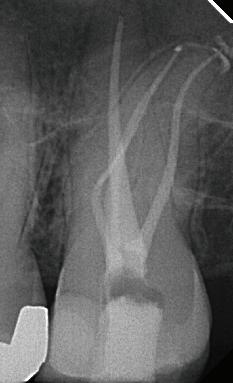

Cleaning. Enhanced.

EdgePRO® provides outstanding Cleaning, Debridement and Disinfection by removing infected tissue, biofilm and smear layer killing up to 99% of bacteria commonly found in the root canals. (1,2,3,4) This should give you the confidence you need to treat even the most complex anatomies.

Endodontics. Streamlined.

EdgePRO® lets “You be You”– shape and obturate the canals the way you want without the need to change your technique. EdgePRO® offers the potential for streamlined workflow and one-visit treatment resulting in reduced treatment time and patient visits.

Technology. Affordable.

EdgePRO® has state-of-the-art technology at more affordable pricing that is as low as 1/3 the cost of other irrigation devices. EdgePRO® gives your practice access to the future of Endodontics and an edge in winning more referral business.